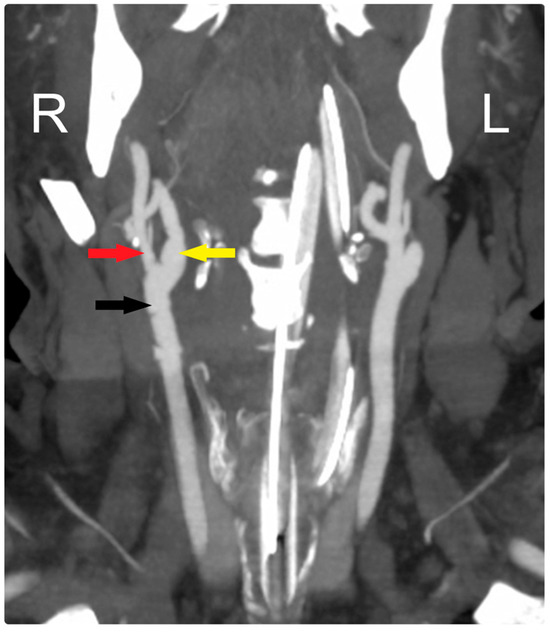

The initial computed tomography angiography (CTA) at an outside hospital showed a completely occluded right internal carotid artery (ICA). The patient was loaded with aspirin and transferred to our institution for further evaluation and treatment. On arrival, additional neuroimaging studies were conducted (Figure 1). Endovascular and open cerebrovascular services were then consulted for a possible thrombectomy and recanalization intervention.

Figure 1. Preoperative neuroimaging. (a) CTA shows complete occlusion of the right ICA; (b) computed tomography perfusion study shows a large region of Tmax > 6 s (time to maximum of the tissue residue function) measuring 223 mL, primarily involving the right middle cerebral artery territory, (c) with a smaller region of CBF< 30% measuring 29 mL in the same territory. The mismatch volume and ratio were 194 mL and 7.7, respectively, with a hypoperfusion index of 0.1; (d) angiogram shows complete occlusion of the right ICA (yellow arrow), patent ECA (red arrow), and CCA (black arrow). R: Right, L: Left, CBF: Cerebral Blood Flow.